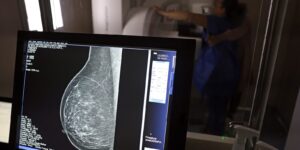

No Outubro Rosa, o Instituto Nacional de Câncer (Inca) estimou 73.610 novos casos este ano no país. É o câncer que mais mata mulheres no Brasil. As mulheres em tratamento pela doença têm o direito de receber o auxílio-doença ou o benefício de prestação continuada.

A vice-presidente da Comissão de Previdência Social Pública da Ordem dos Advogados do Brasil do Rio de Janeiro (OAB-RJ), Danielle Guimarães, destaca que o câncer de mama é uma das doenças que mais afetam mulheres no Brasil, impactando não apenas a saúde física e emocional, mas também a capacidade de trabalho e a segurança financeira das pacientes.